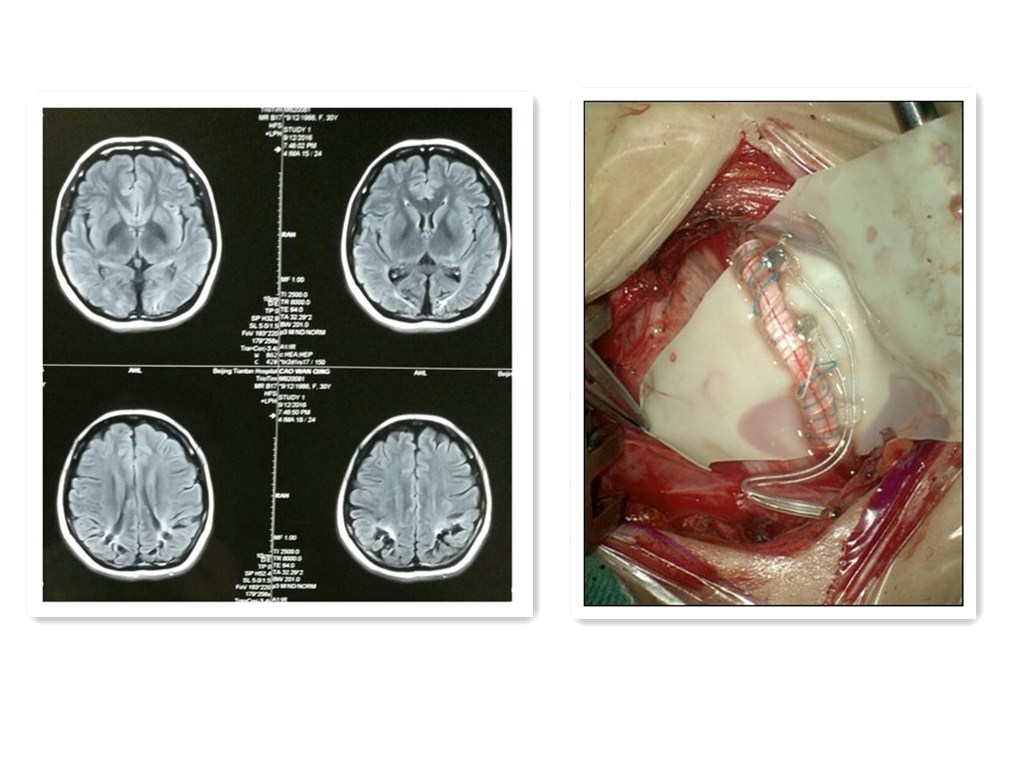

十岁小大人四经生死 高位颈髓肿块终切除